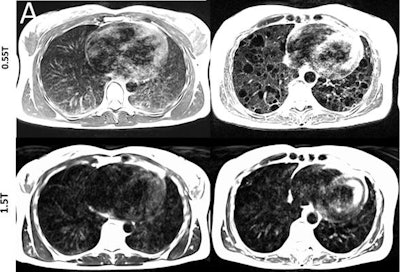

A total of 83 0.55-tesla MRI scans were performed on 83 subjects (mean age, 34 ± 13 years). Depending on the scan, they were fitted with phased-array receiver coils, such as 18-channel spine array, six-channel body array, and/or a 16-channel head array. Subjects also underwent 1.5-tesla scans for comparison MR images.

In addition, compared with 1.5 tesla, image distortion was reduced at 0.55 tesla in scans of the lungs, upper airway, cranial sinuses, and intestines due to improved field homogeneity. In particular, oxygen inhalation generated lung signal enhancement of 19% (± 11) at 0.55 tesla, compared with 7.6% (± 6.3) at 1.5 tesla.